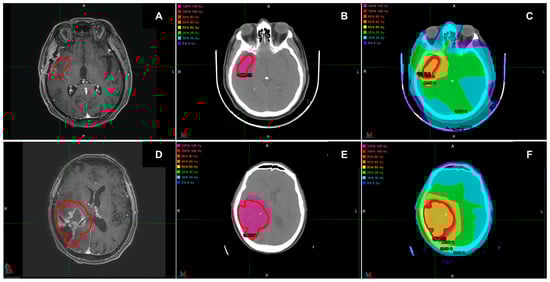

2.1. MRI and Target Delineation

2.2. Treatment Planning

2.3. Dose Calculation with 90Y-Labeled PVA-MBs

2.4. Dose Calculation with VMAT